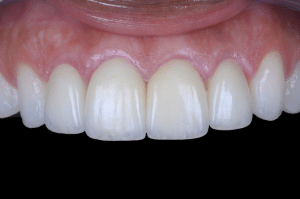

Fig 10

Aspect clinique le jour de la mise en place des prothèses d’usage individuelles.